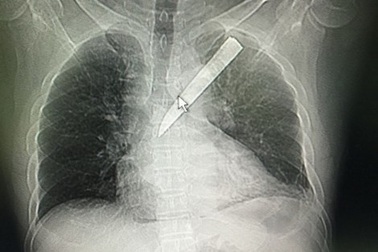

Mang lưỡi dao gãy trong phổi đi cấp cứuChiều ngày 1), TS-BS Nguyễn Văn Châu, Giám đốc BV Đa khoa Xuyên Á (huyện Củ Chi, TP.HCM), cho biết bệnh viện vừa phẫu thuật cấp cứu khẩn cấp, cứu sống bệnh nhân Nguyễn Thanh Kỳ (47 tuổi, ngụ tại huyện Gò Dầu, Tây Ninh) vì bị đâm thủng phổi, lưỡi dao Thái Lan gãy nằm luôn trong ngực.